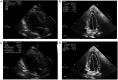

Figures